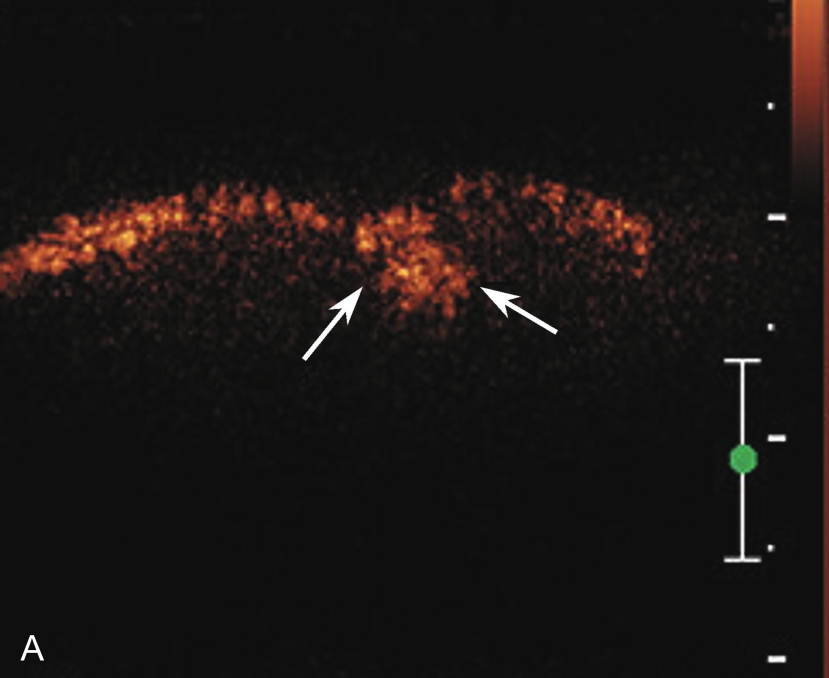

横放在肩关节前方,选择肩峰滑囊较厚或囊液较多处为靶目标(图2-1-2)。

▲ 图2-1-2 肩峰下-三角肌下滑囊炎超声图

星号:肩峰下滑囊增厚伴滑膜增生